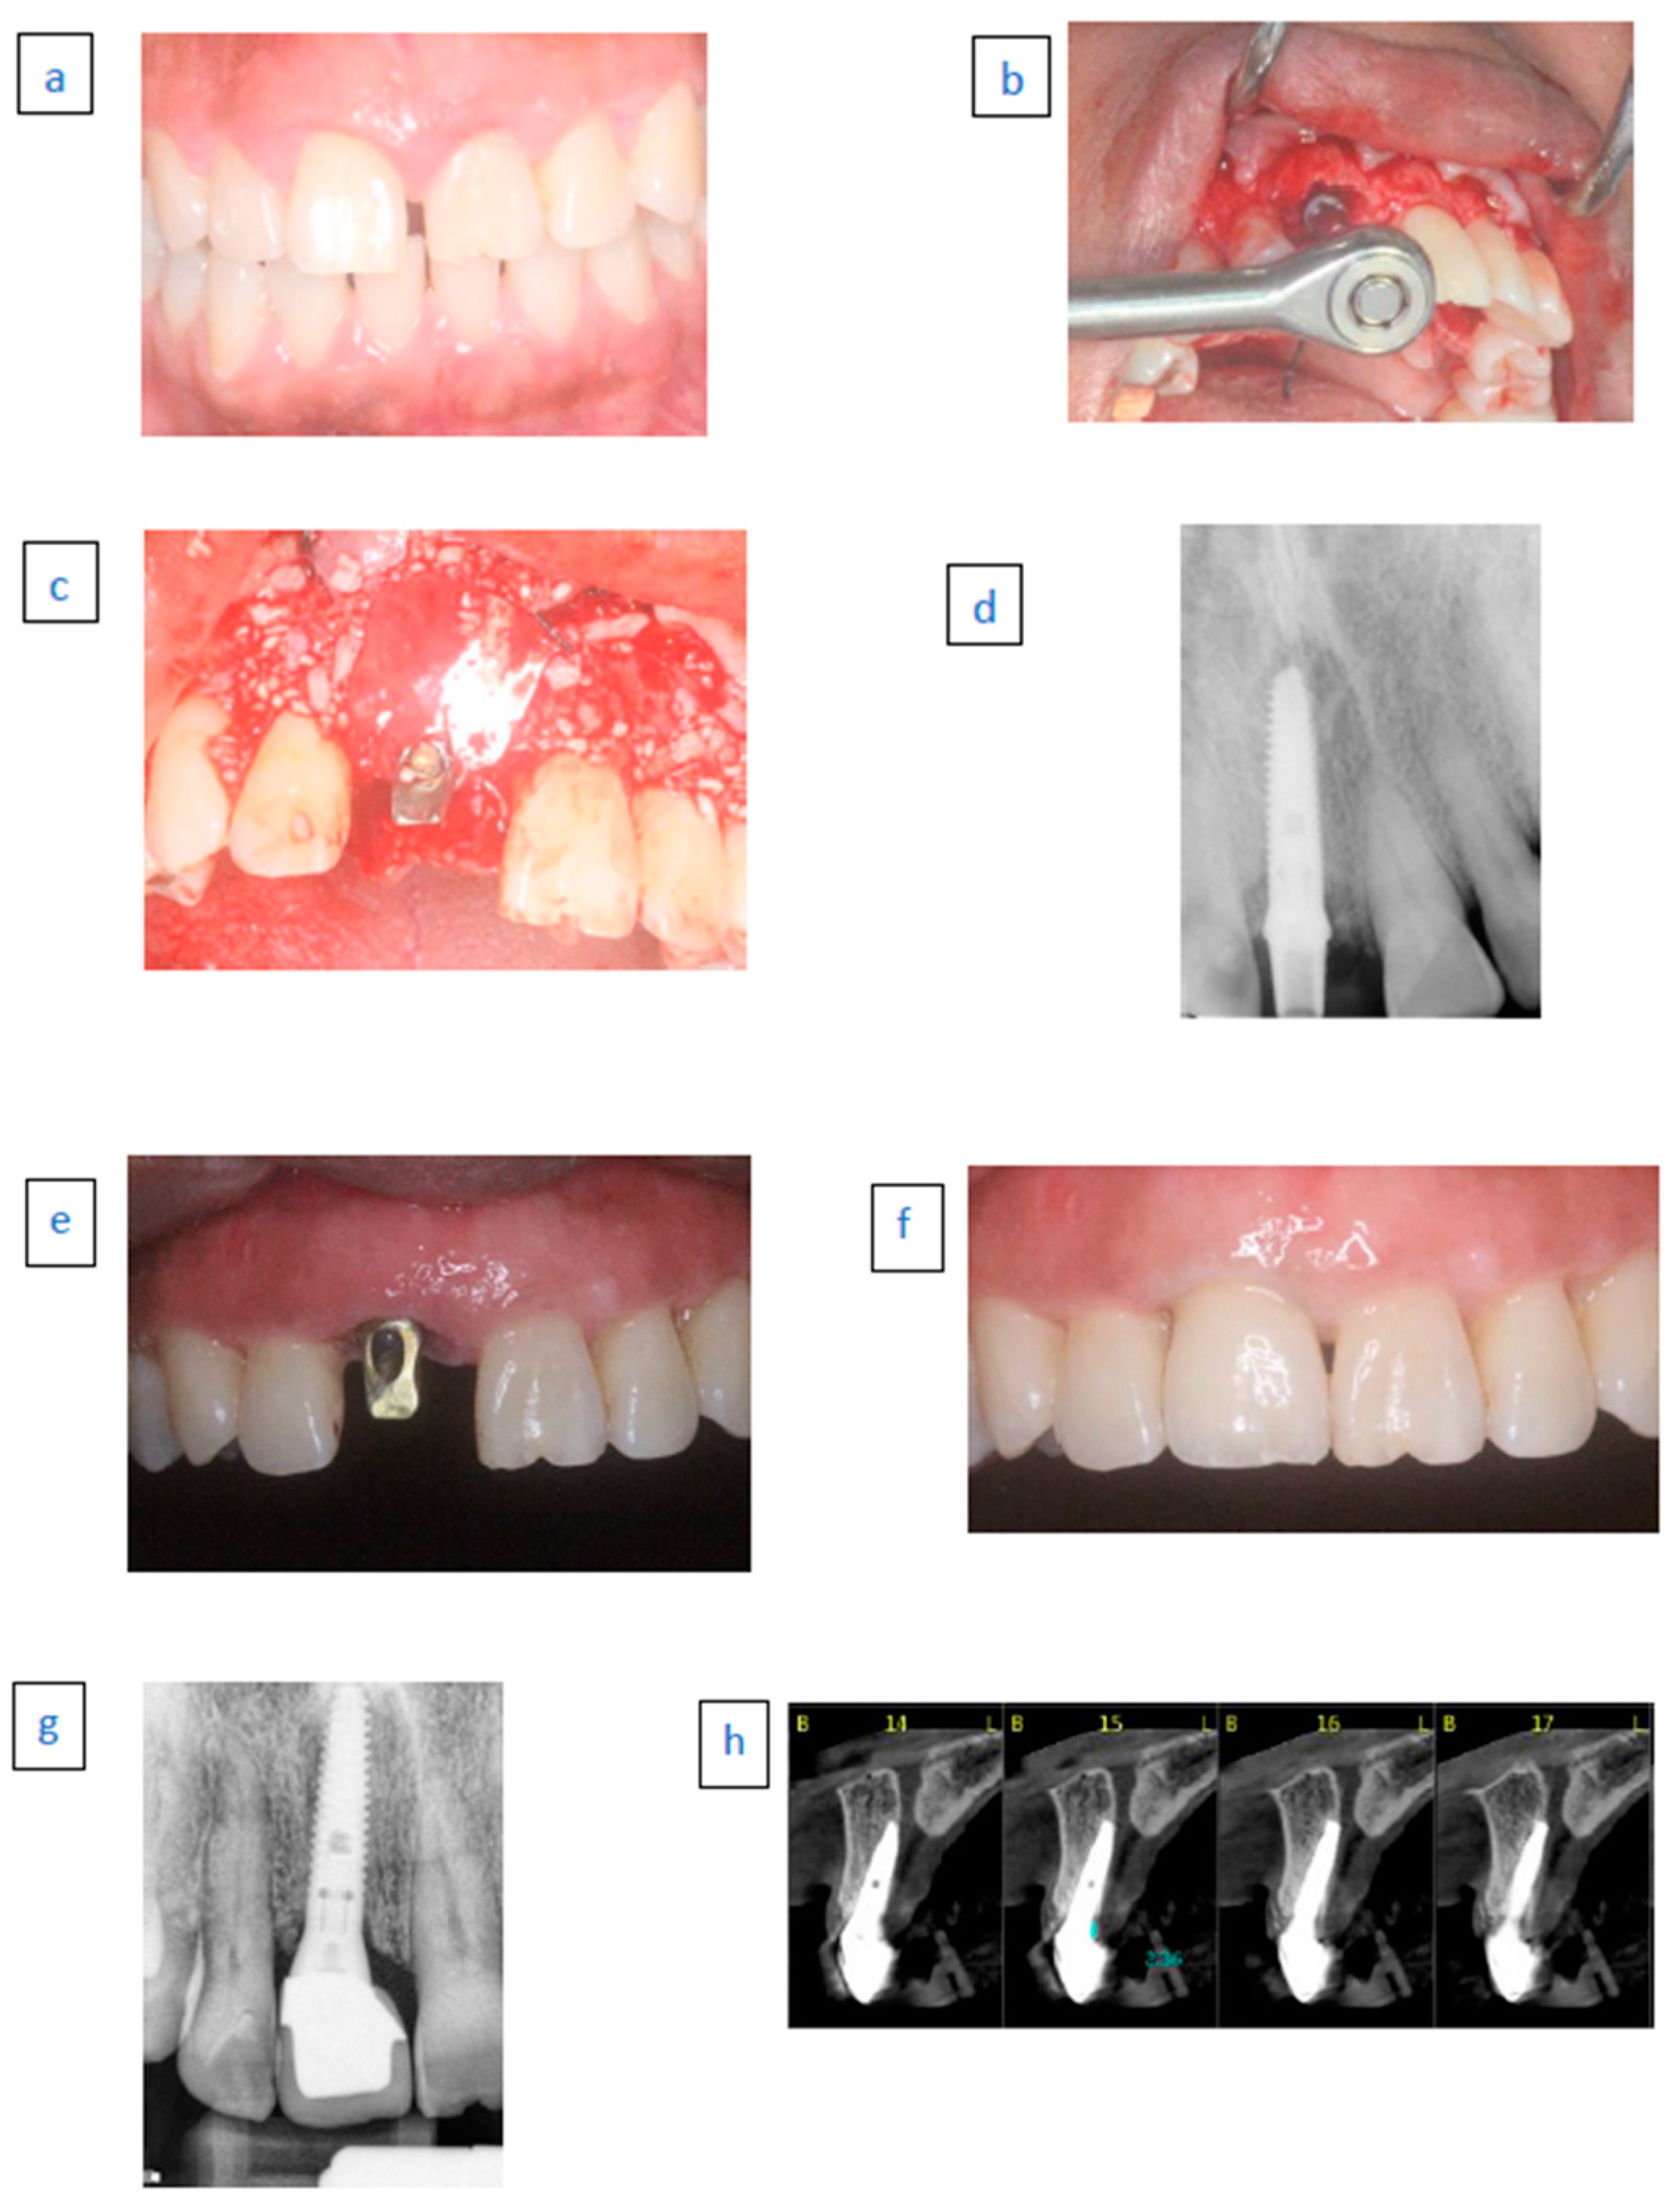

- A 65-year-old female patient.

- Nonsmoker with chronic advanced periodontitis.

- Case 1 (a) A hopeless second right premolar due to vertical root fracture.

- Case 1 (b) Immediate implant placement with temporary abutment.

- Case1 (c) Follow-up examination after 38 months.

- A 56-year-old male patient.

- Case 2 (a) A hopeless left maxillary first premolar tooth due to vertical fracture.

- Case 2 (b) Immediate implant placement with temporary abutment. Radiopaque material demonstrated above the implant neck.

- Case 2 (c) Follow-up examination after 36 months.

- A 46-year-old female.

- Nonsmoker with generalized aggressive periodontitis.

- Case 3 (a) Hopeless left central incisor due to advanced bone loss.

- Case 3 (b) Immediate implant placement with temporary abutment. Radiopaque material demonstrated above the implant neck.

- Case 3 (c) Follow-up examination after 96 months.

- A 76-year-old female.

- Case 4 (a) Hopeless left lateral first incisor due to external root resorption.

- Case 4 (b) Immediate implant placement with temporary abutment.

- Case 4 (c) Follow-up examination after 24 months.